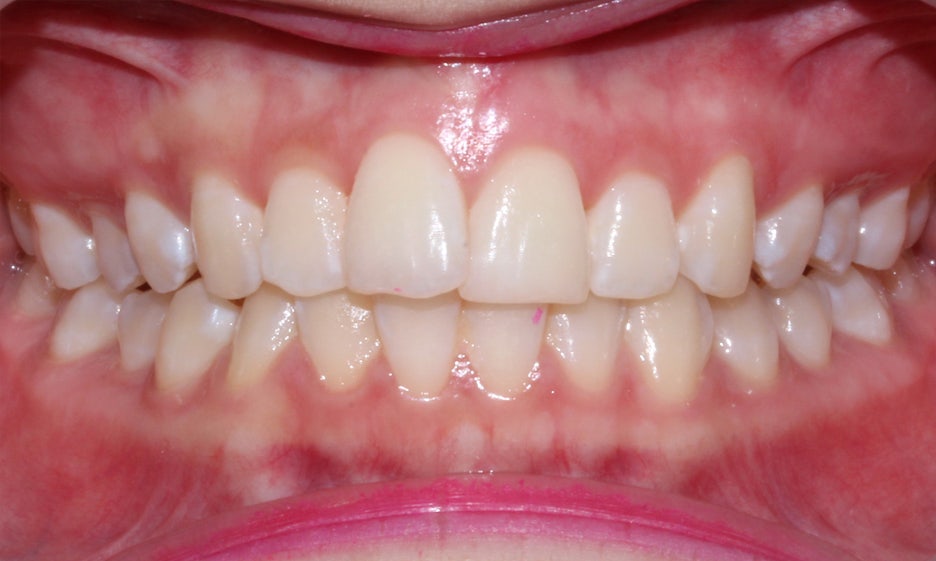

앞니돌출 교정 전

2D치과

반포치과 환자분의 앞니돌출 교정 전

입술 모습을 보면 튀어나온 중절치로 인해

윗입술이 두꺼워 보이고 돌출감이 있는 모습인데요,

돌출형 구강 구조를 가진 환자분들의 경우

입술을 다물었을 때 입매가 튀어나오고

부자연스러워 보일 수 있습니다.

미소를 보였을 때 노출되는 스마일라인

치아를 보면 상악의 경우 전치부 치열이

삐뚤거리고 좌측 중절치가 튀어나온 모습인데요,

앞니가 서로 겹쳐져 있기 때문에 치아 관리가

어렵고 치석이 끼거나 충치가 발생할 가능성이 높습니다.